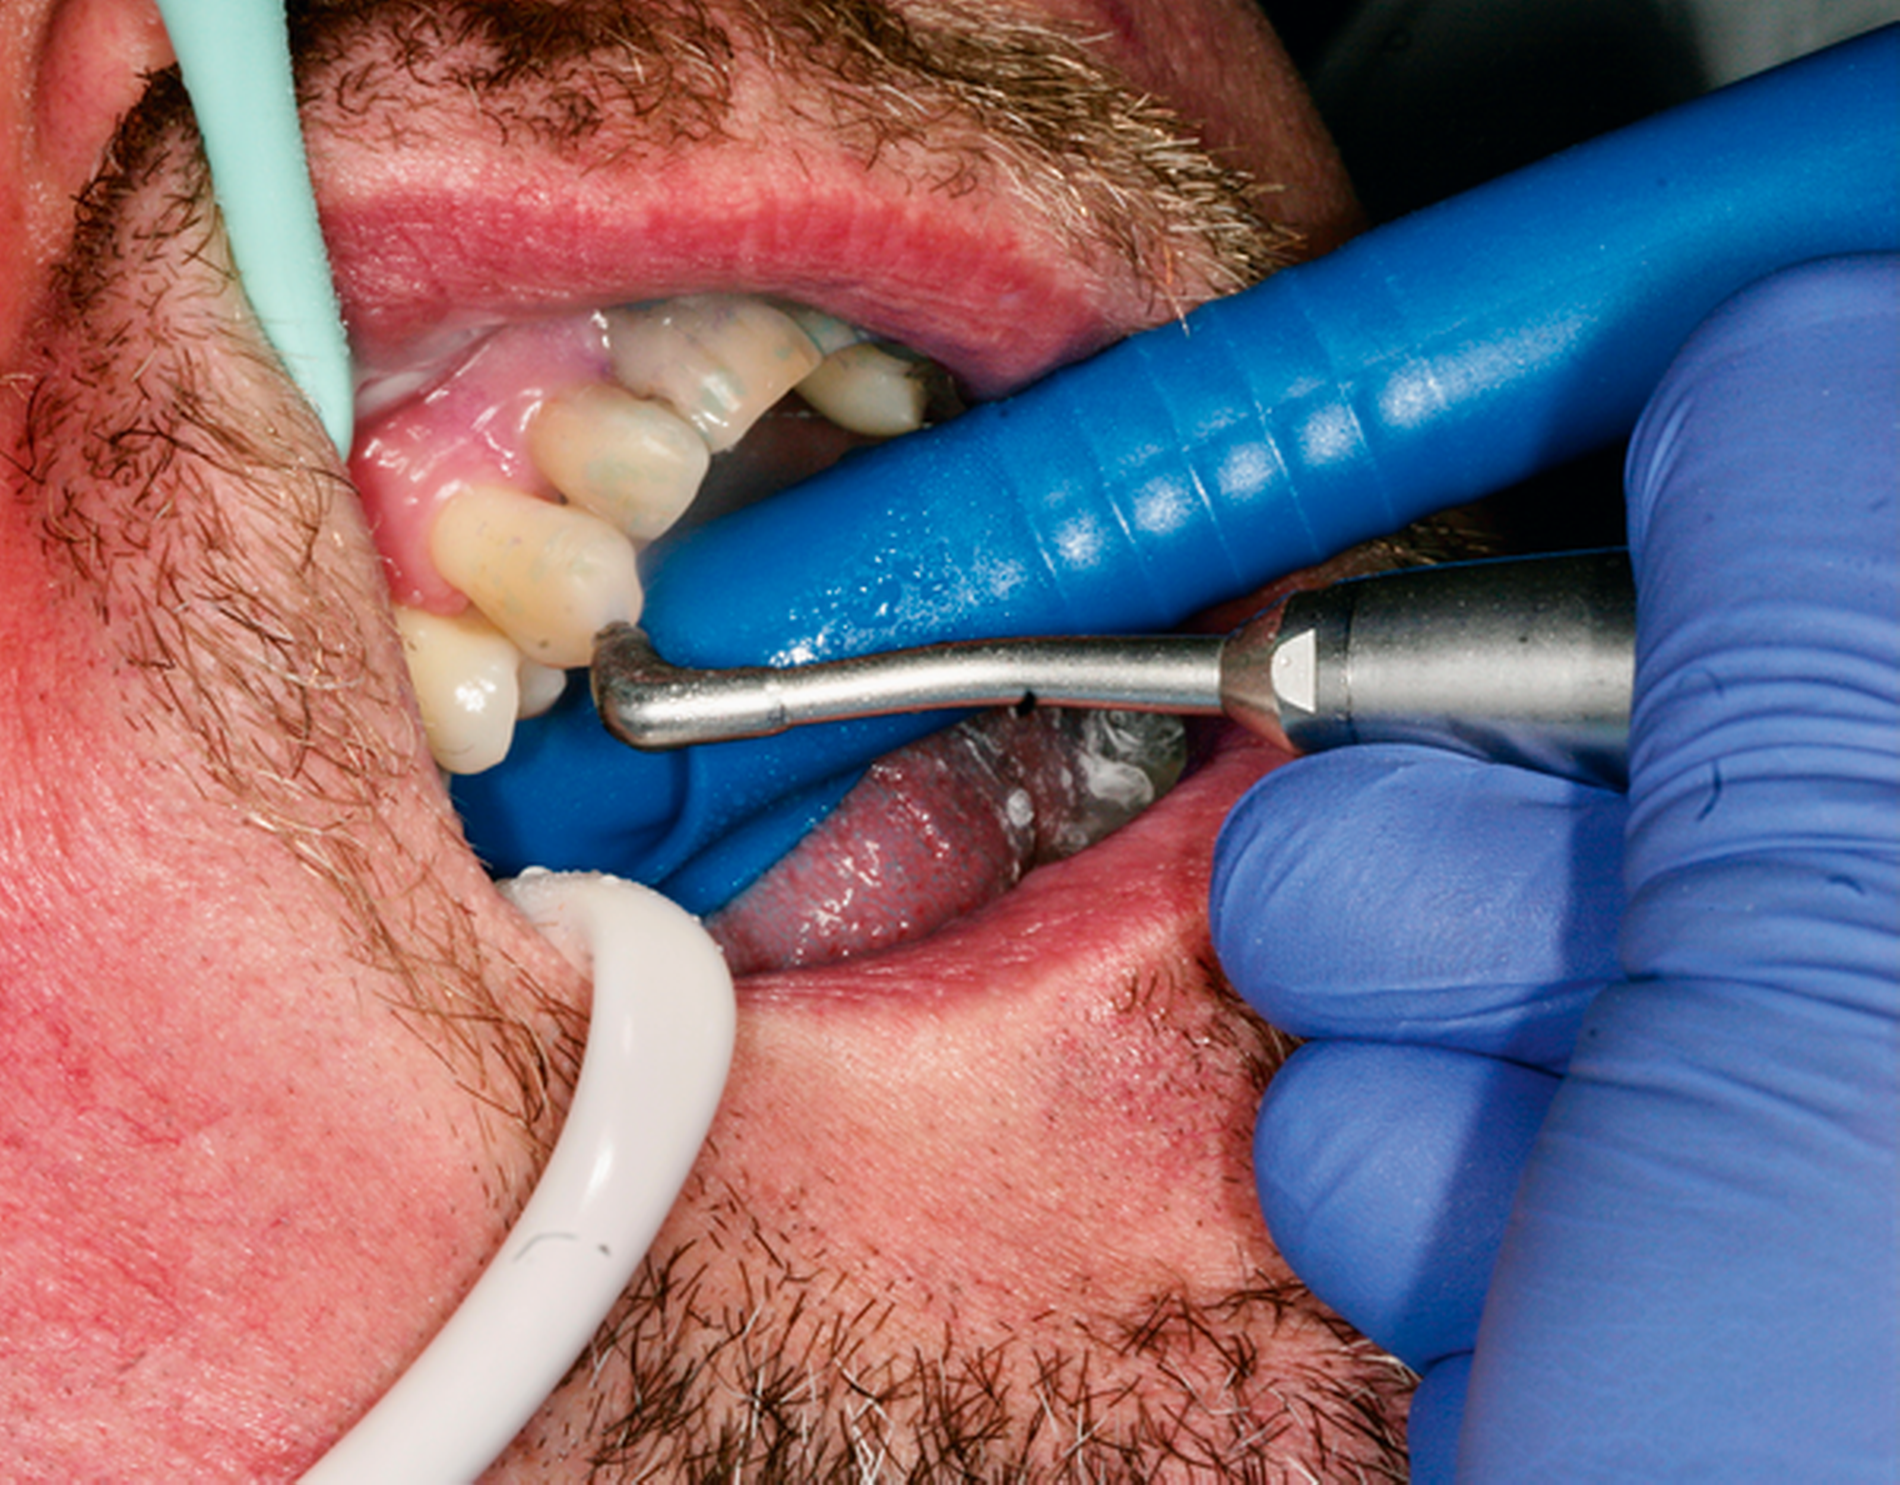

Abb. 2: Professionelle mechanische Plaquereduktion während einer UPT-Sitzung bei einem 50-jährigen Patienten mit reduziertem, aber gesundem Parodont im dritten Jahr nach zweiter Therapiestufe:

Als zentraler Bestandteil einer regelmäßig durchgeführten UPT ist die professionelle mechanische Plaquereduktion (PMPR) mit dafür verantwortlich, dass kurz- und auch langfristig nachweislich geringere Zahnverlustraten und geringere Änderungen des klinischen Attachmentlevels (CAL) erreicht werden können [Heasman et al., 2002; Trombelli et al., 2015]. Es muss aber beachtet werden, dass in den meisten Studien die PMPR in der UPT in Kombination mit anderen Interventionen (zum Beispiel wiederholte Mundhygieneinstruktionen, zusätzliche aktive Therapie) untersucht wurde, was einen direkten Rückschluss auf deren alleinigen Effekt für den Zahnerhalt und die Stabilität der parodontalen Zustände sowie deren Einflussgröße erschwert [Trombelli et al., 2015].